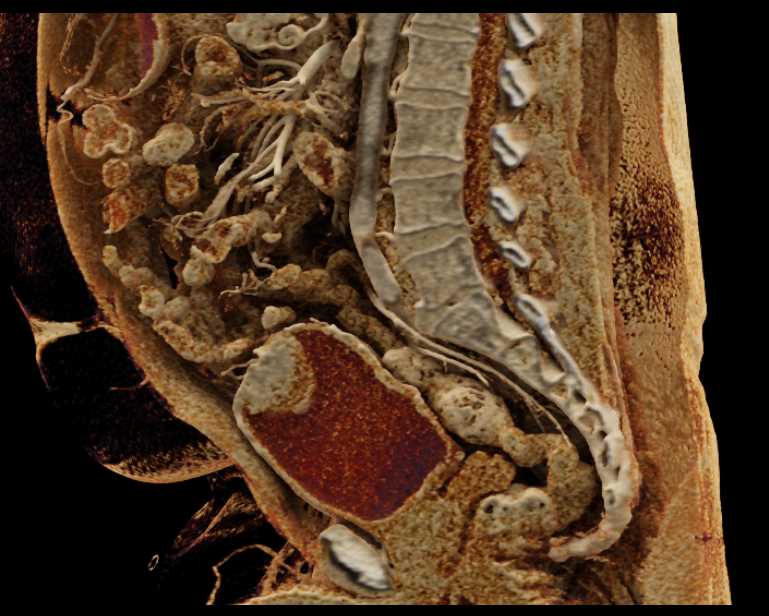

Bladder Cancer with Active Bleed